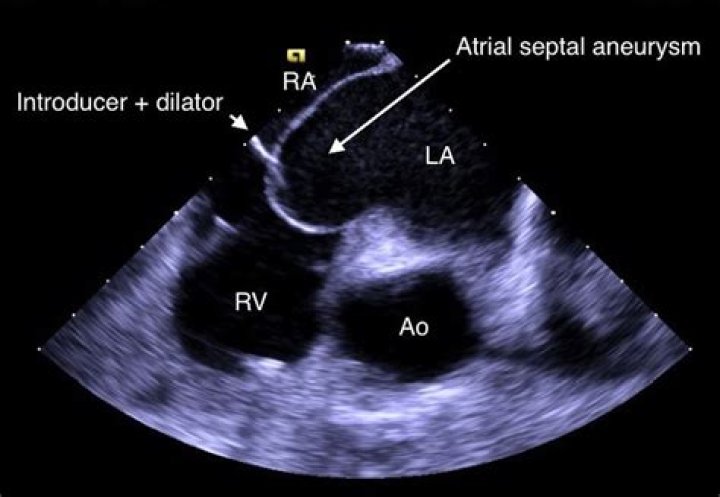

The interatrial septum is the thin wall that separates the upper atrial cavities of heart. When it appears elongated and “floppy” on cardiac ultrasound, we call it “aneurysmal”. This is a condition that some people are born with. It alone portends no prognostic risk.

An aneurysm of the interatrial septum is an infrequent finding in adult patients. Atrial septal aneurysm is a congenital malformation of the septum primum layer of the interatrial septum but differences between interatrial pressure forces have also been reported as a cause of its development.

Introduction. Atrial septal aneurysm (ASA) is a congenital deformity of interatrial septum consisting redundant and mobile interatrial septal tissue in the region of fossa ovalis with bulging into the right or left atrium and sometimes oscillating between both atria.

What does Hypermobile interatrial septum mean?

It is a localized bulging of the inter-atrial septum into either or both atria during the cardiac cycle. ASA has been reported as an unexpected finding during autopsy but may also be diagnosed in living patients by echocardiographic techniques...